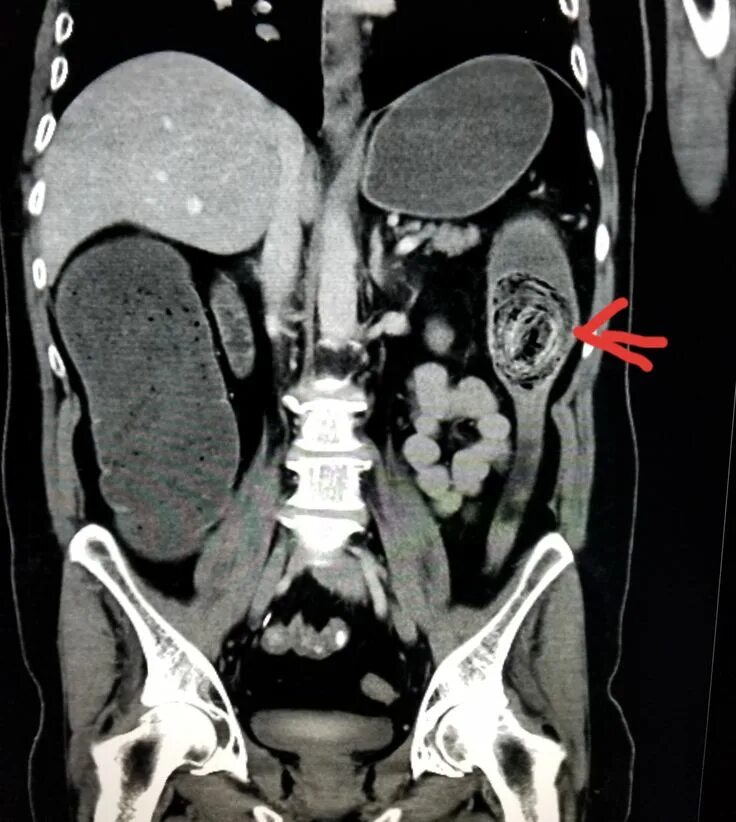

Ct search